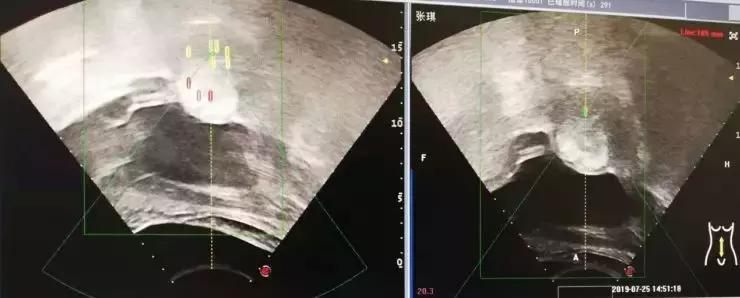

下面四组影像学资料为其中一名子宫肌瘤患者在治疗前、治疗中以及治疗后的影像学表现。

消融术后表现